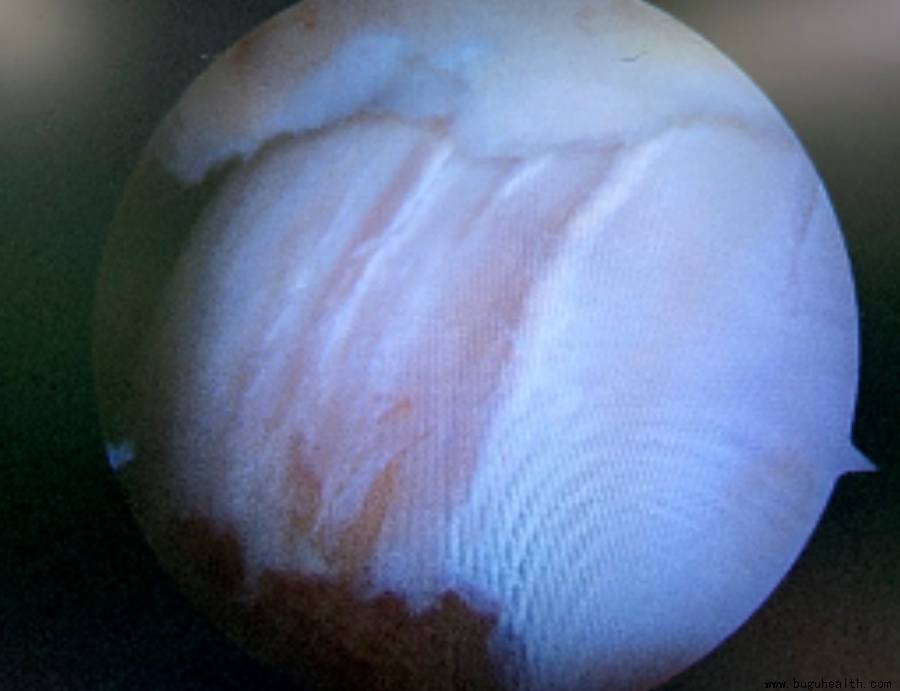

在一些长期踝关节不稳定的患者中,距骨软骨表面常常会出现下面的软骨磨损,引起踝关节的疼痛。

布骨医学科普、肌骨康复、布骨康复